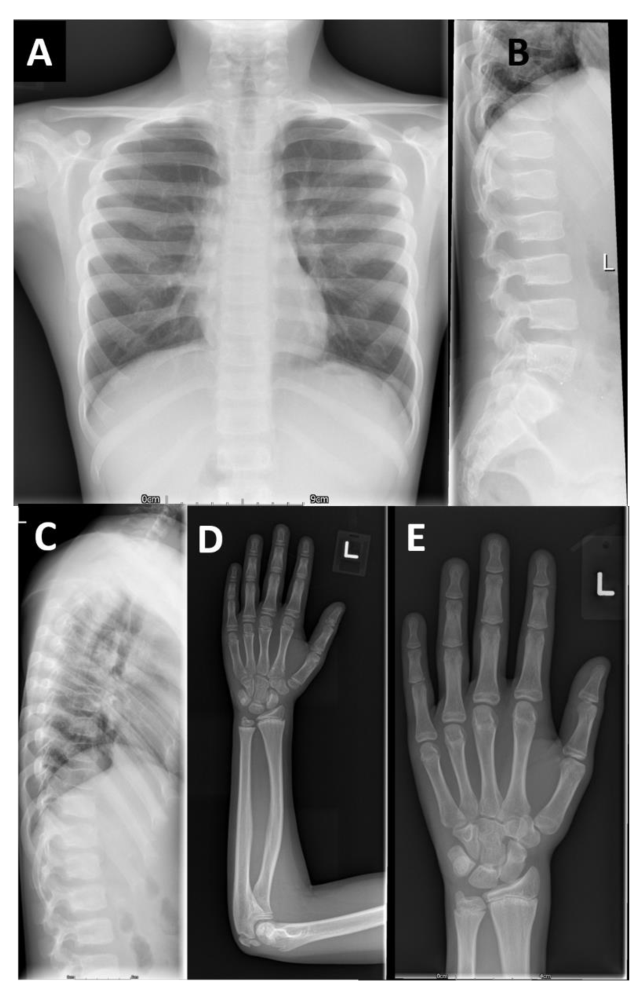

本研究提供了两个家系的详细表型信息,并与两个已发表的病例进行了比较。F2-V-3的放射学发现与之前描述的“先证者1”的放射学发现非常相似,这并不令人惊讶,因为这两个人都有相同的纯合子p.Arg569*。相反,PRKG2家族1有一致的放射学表型,不同于先前报道的AMDP和AMDM。

两个PRKG2变异家族的影像学表现

本文报告的三兄弟 (F1-IV-3、IV-6和IV-7)除了个别F1-IV-7有轻微的脚趾缩短外,没有肢端缩短 (Acromesomelic shortening)的证据。主要发现是颈椎病伴有椎体前突、股骨颈细长、干骺端不规则 (最明显的是桡骨和尺骨)和横纹(Striations)。其中一个儿童的远端指骨干骺端呈圆锥形,但是不显著。综上所述,家族1表现为以脊柱干骺端发育不良 (Spondylometaphyseal dysplasia)为特征的骨骼表型,而不是像AMDP和AMDM所预期的肢端发育不全。

F1- IV- 7的额外影像学表现